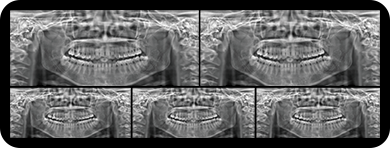

标配专业正畸软件

支持自动描点功能

精准定位

临床样片